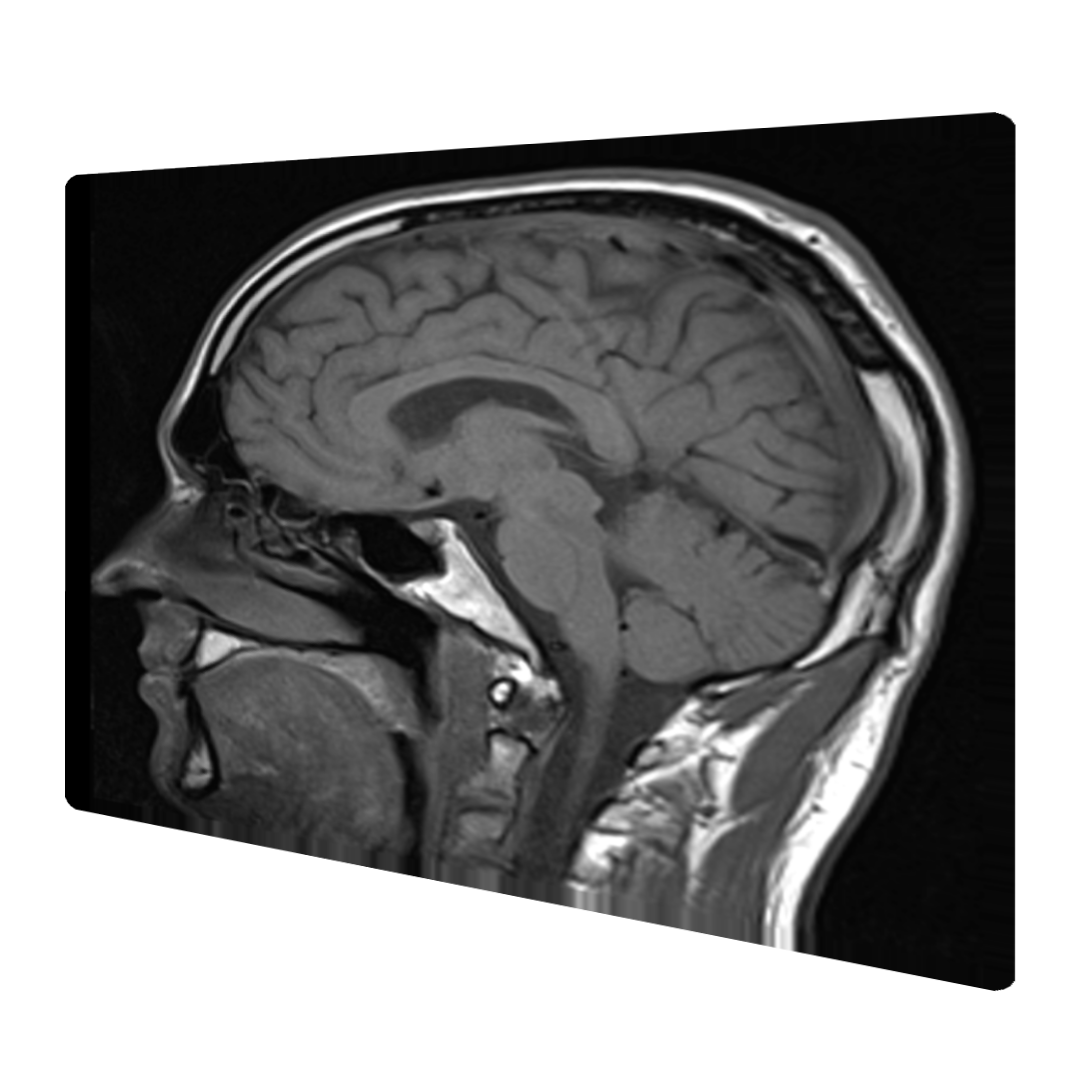

Univerzitní vzdělání v oborech neklinické medicíny (neurověda a neurodegenerace) a informatiky.

• Neuroscience

• Neurodegeneration

The University of Sheffield je výzkumná univerzita s celosvětově renomovaným pracovištěm zabývajícím se výzkumem neurodegenerativních onemocnění - Sheffield Institute for Translational Neuroscience (SITraN).